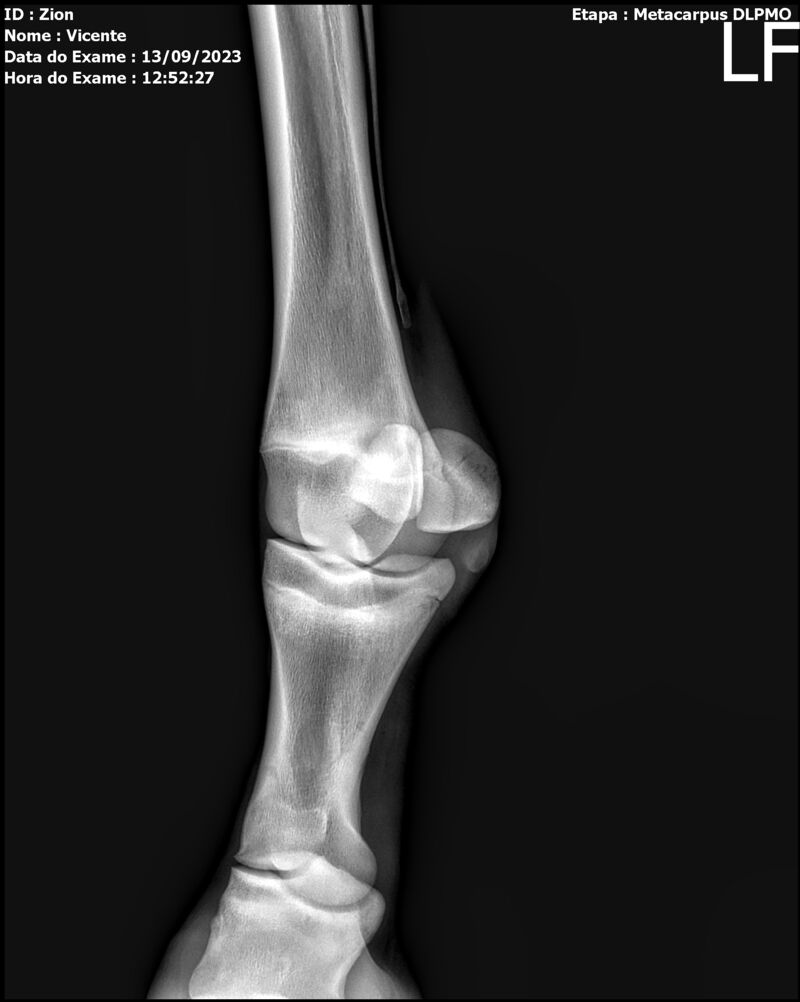

ZION ZC

Raça: BRASILEIRO DE HIPISMO

Sexo: MACHO - POTRO

Nascimento: 17/12/2022

Altura Aproximada: 1,51

Pel.: CASTANHO

Registro: EM AND

Vend.: VICENTE CONTE

Local : PORTO FELIZ/SP